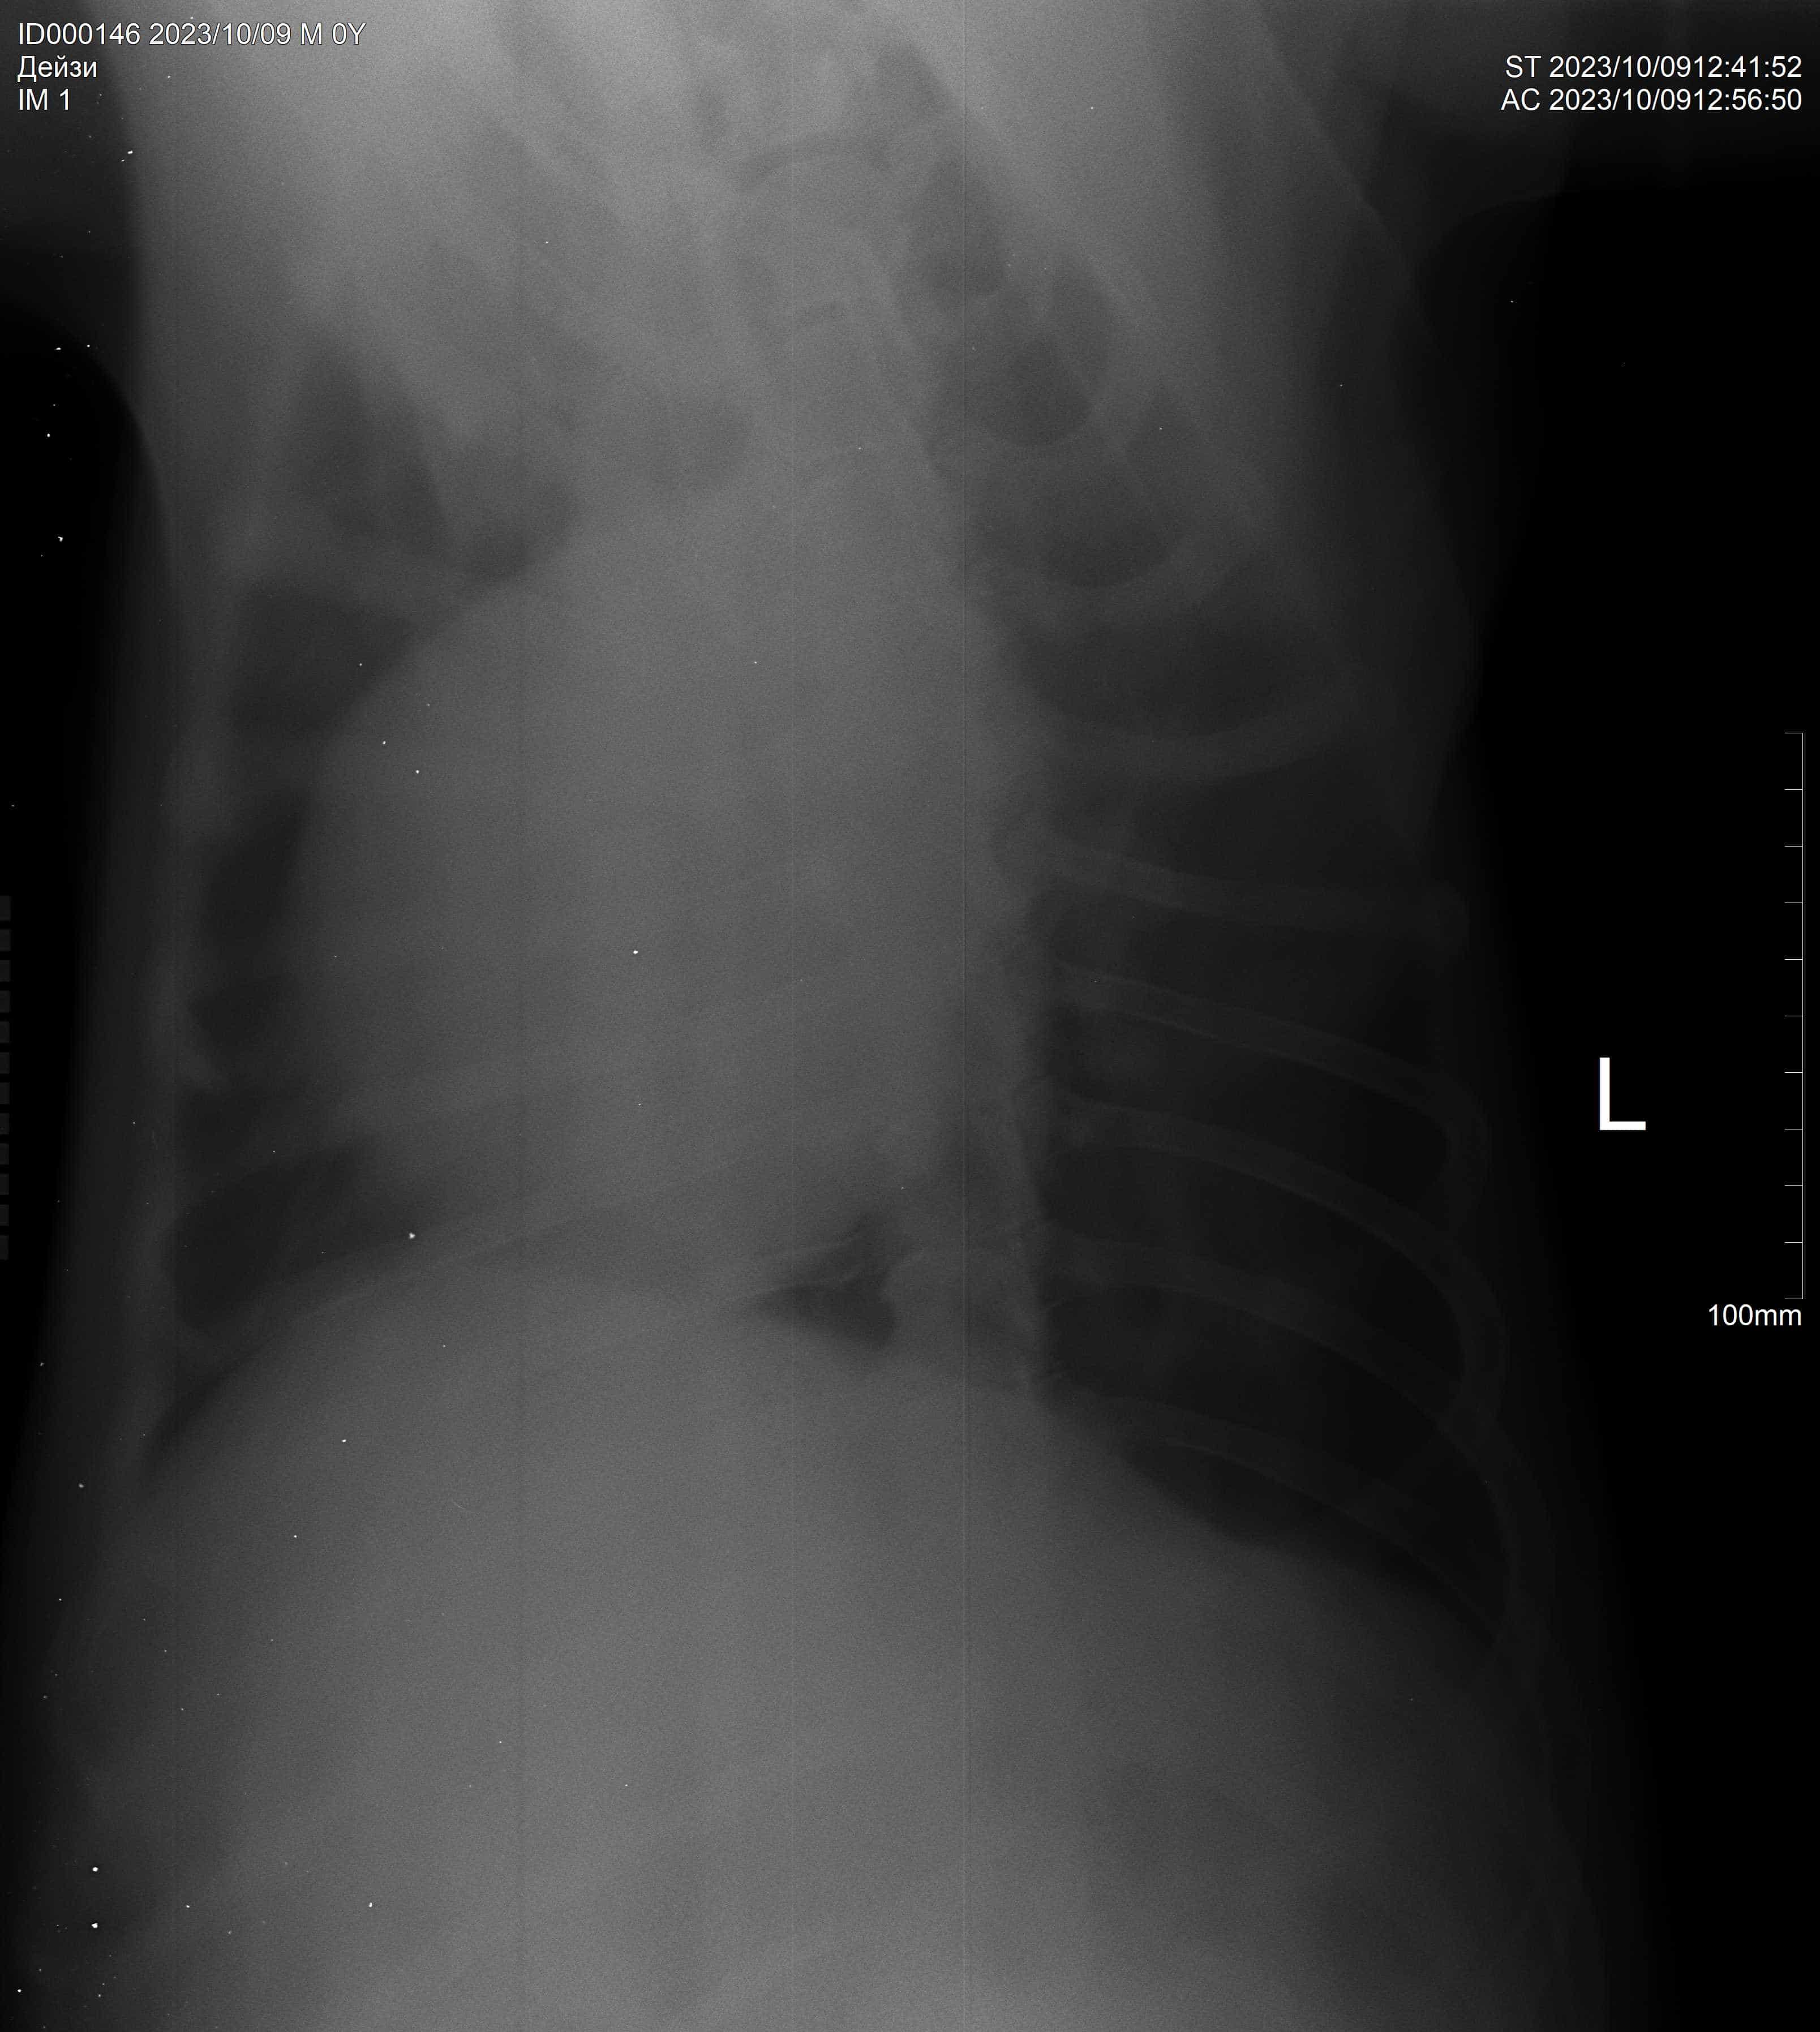

Операция и кардиография